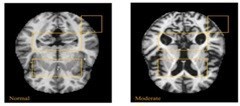

In AD affected brain the ventricles in center of the region enlarges and the cortical gray area in the corners of the brain reduces [9].

Non-demented very mild mild moderate